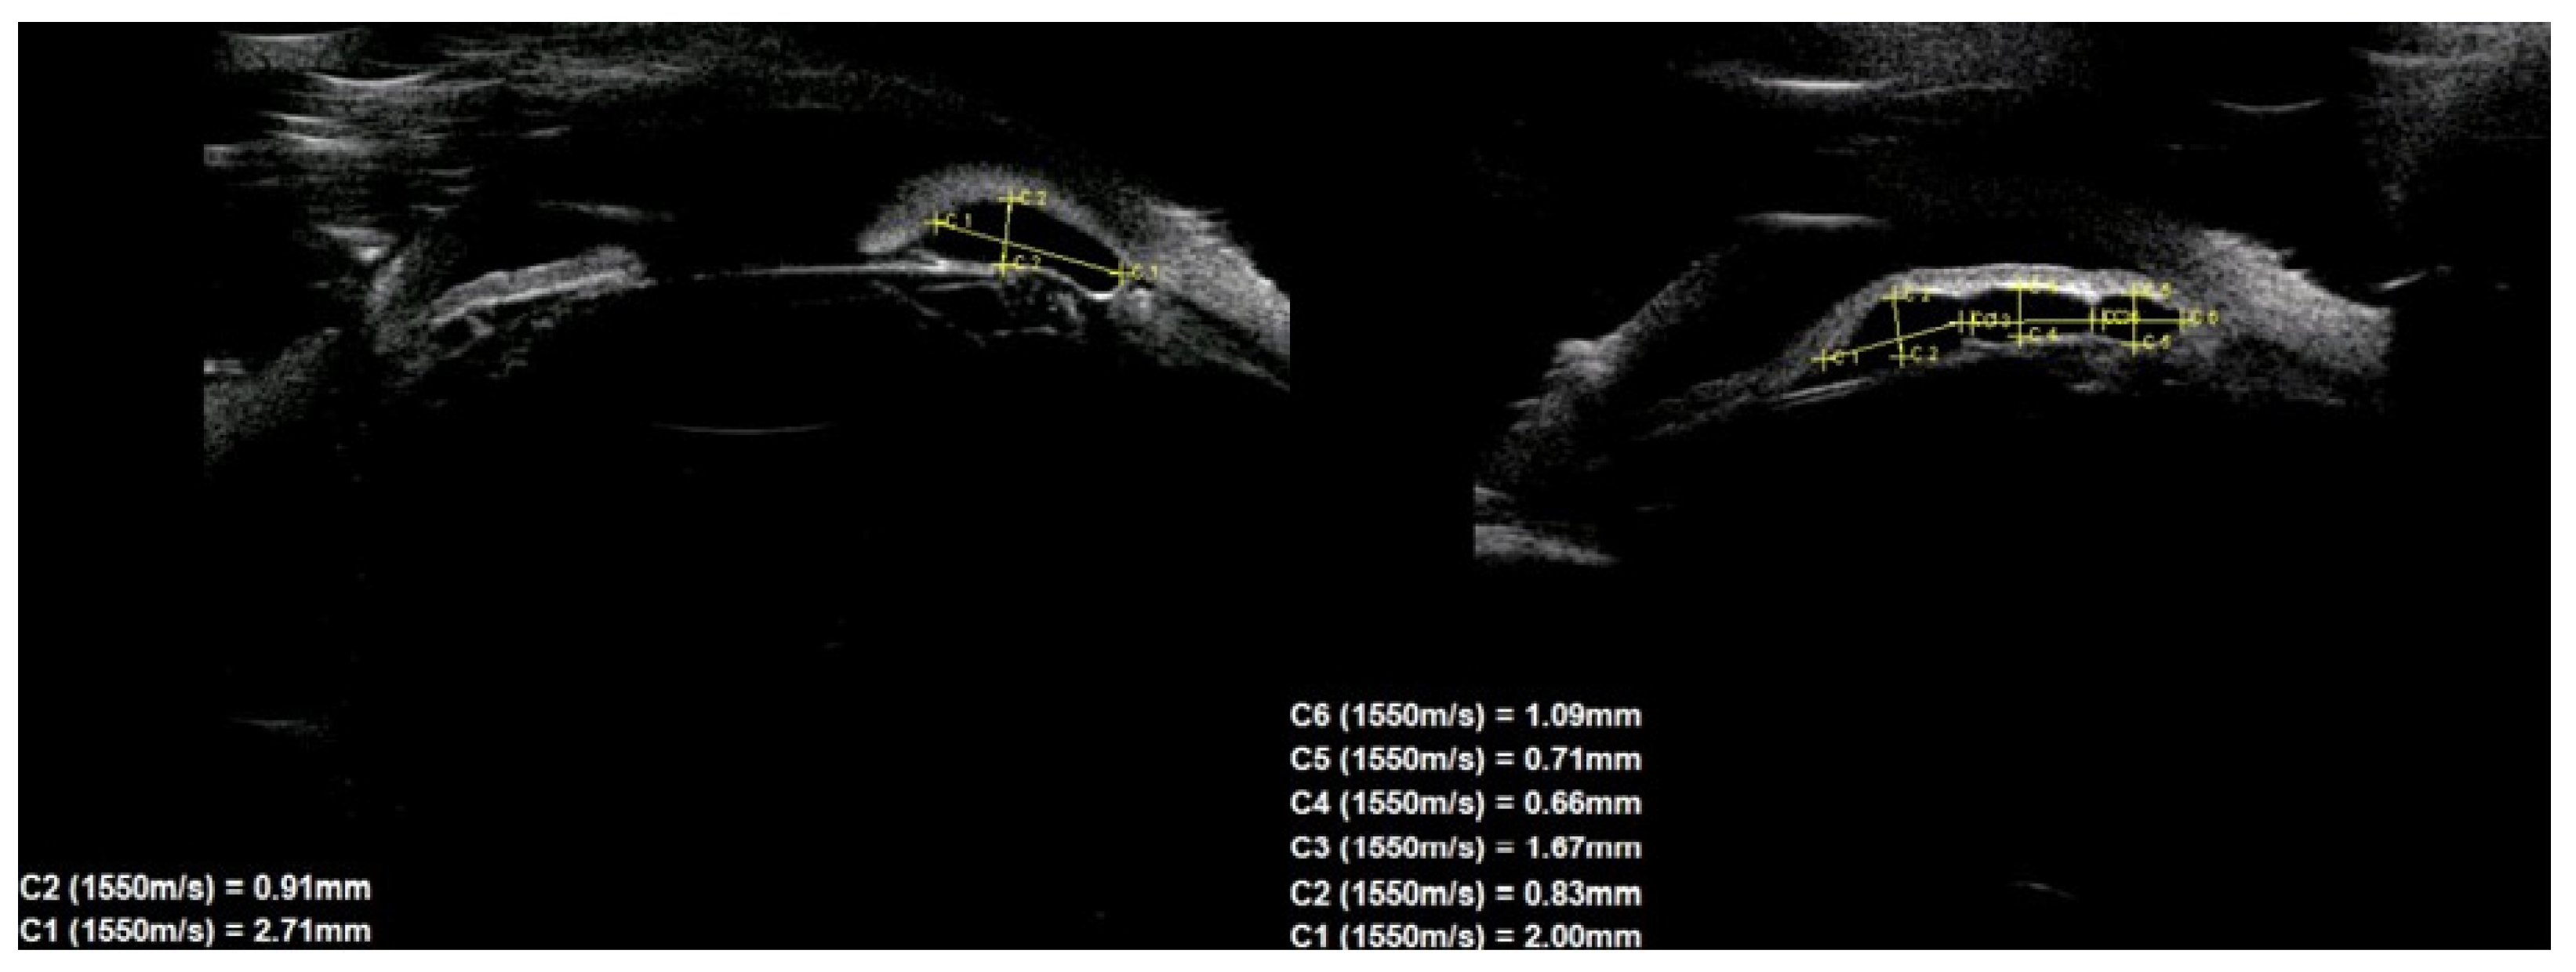

UBM was performed in all patients by two experienced researchers (J.K., Ł.L.), according to the technique described earlier [21] with a 50 MHz transducer. Images were obtained at the radical meridian conducted through the largest tumor thickness using an eyecup filled with 1% methylcellulose and distilled water. Ultrasound images were assessed for the type of lesion, size, location, echogenicity, external structure (regular/irregular), iris pigment flap eversion, and documented growth. On this basis, 39 patients with iris cysts were identified from the entire group of tumors in the anterior segment of the eye. The dimensions of the cysts were defined as the largest dimension of the base and the greatest dimension of the height, drawn perpendicular to each other, according to the previously described technique [22]. The position of the cysts was assessed in two ways: peripheral, central (at the pupillary margin), and midzonal, and divided into quadrants. The individual quadrants were determined using a clock face, following the rules: (1) upper-nasal quadrant in the right eye: 12.00–3.00, and in the left eye: 9.00–12.00; (2) inferno-nasal quadrant in the right eye: 3.00–6.00, and in the left eye: 6.00–9.00; (3) upper temporal quadrant in the right eye: 9.00–12.00, and in the left eye: 12.00–3.00; and (4) inferno-temporal quadrant in the right eye: 6.00–9.00, and in the left eye: 3.00–6.00. In isolated cases, where the cyst was on the border of two quadrants, it was assigned to the quadrant containing the larger part of it. Multiple cysts were defined as the presence of three or more cysts in one eye or multichamber cysts [6].

The cyst size measurements based on the UBM test are presented in Table 1. There were no statistically significant differences in cyst size according to sex.

Table 1. Cyst size measured with ultrasound biomicroscopy in 39 patients depending on sex.

SexBase Width (mm)Height (mm)

nMean (±SD)Median (Range)pnMean (±SD)Median (Range)p

The group392.07 ± 0.911.87 (1.04–5.64) 391.2 ± 0.61.09 (0.63–4.04)

Female272.95 ± 2.342.29 (0.96;3.87)0.512271.40 ± 0.901.09 (0.48;2.60)0.886

Male123.03 ± 2.312.41 (1.31;4.33)121.33 ± 0.801.21 (0.53;2.93)